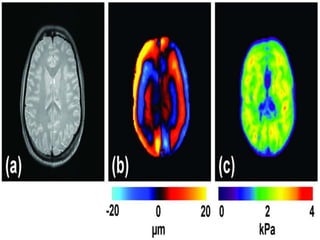

Hematoma. (a) B-mode US image of the breast demonstrates a superficial

heterogeneous mass. (b) US elastogram shows that the lesion is stiff but

measures smaller than on the B-mode image. Dotted lines indicate

measurements of the lesion diameter: 11.0  5.3 mm in a and 10.2  4.2 mm in b.

The distance ratios were calculated as 10.2  11.0 = 0.93 (for the long-axis

dimension) and as 4.2  5.3 = 0.79 (for the short-axis dimension). At physical

examination, skin discoloration was noted in the corresponding area, a finding

consistent with a hematoma.